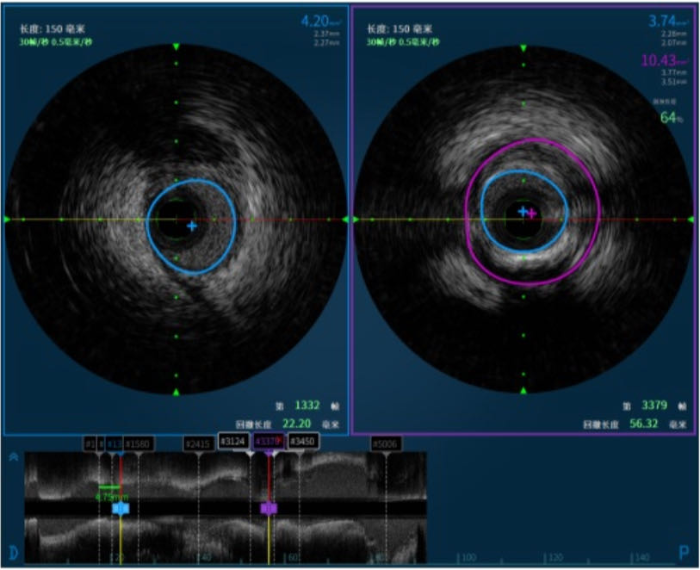

何麗決定對病變部位實施血管内超聲檢查術(shù),檢查過程中發現,王某血管病變處多爲負性重構所緻,且血管斑塊負荷64%,管腔面積3.74mm²,暫無需介入治療,大(dà)大(dà)減輕了王某的心理(lǐ)和經濟負擔。

血管内超聲(IVUS)通過導管技術(shù)将微型超聲探頭送入血管腔内,通過聲波掃描和反射,從(cóng)而提供在體(tǐ)血管腔内影(yǐng)像,能清晰顯示管壁結構的厚度、管腔大(dà)小和形狀等,精确地測量血管腔徑及截面積,甚至可(kě)以辨認鈣化、纖維化和脂質池等病變,發現冠脈造影(yǐng)不能顯示的血管早期病變。

傳統的冠脈造影(yǐng),隻能顯示管腔的情況,宛如(rú)盲人(rén)摸象,呈現病變并不清晰明了。相(xiàng)比之下,血管内超聲(IVUS)作(zuò)爲一種新的診斷方法,是将發絲般粗細的超聲探頭,精準送入冠心病患者的靶血管内,在血管腔内進行360度全方位多層次的掃描。通過電子顯示屏,清晰顯示心髒冠狀動脈的結構和病變情況,構造一個立體(tǐ)的心髒冠狀動脈地圖,指導确立最合适的治療方案,并可(kě)在支架植入後再次觀察指導支架植入的“精修微調”,減少支架再狹窄的發生(shēng)。